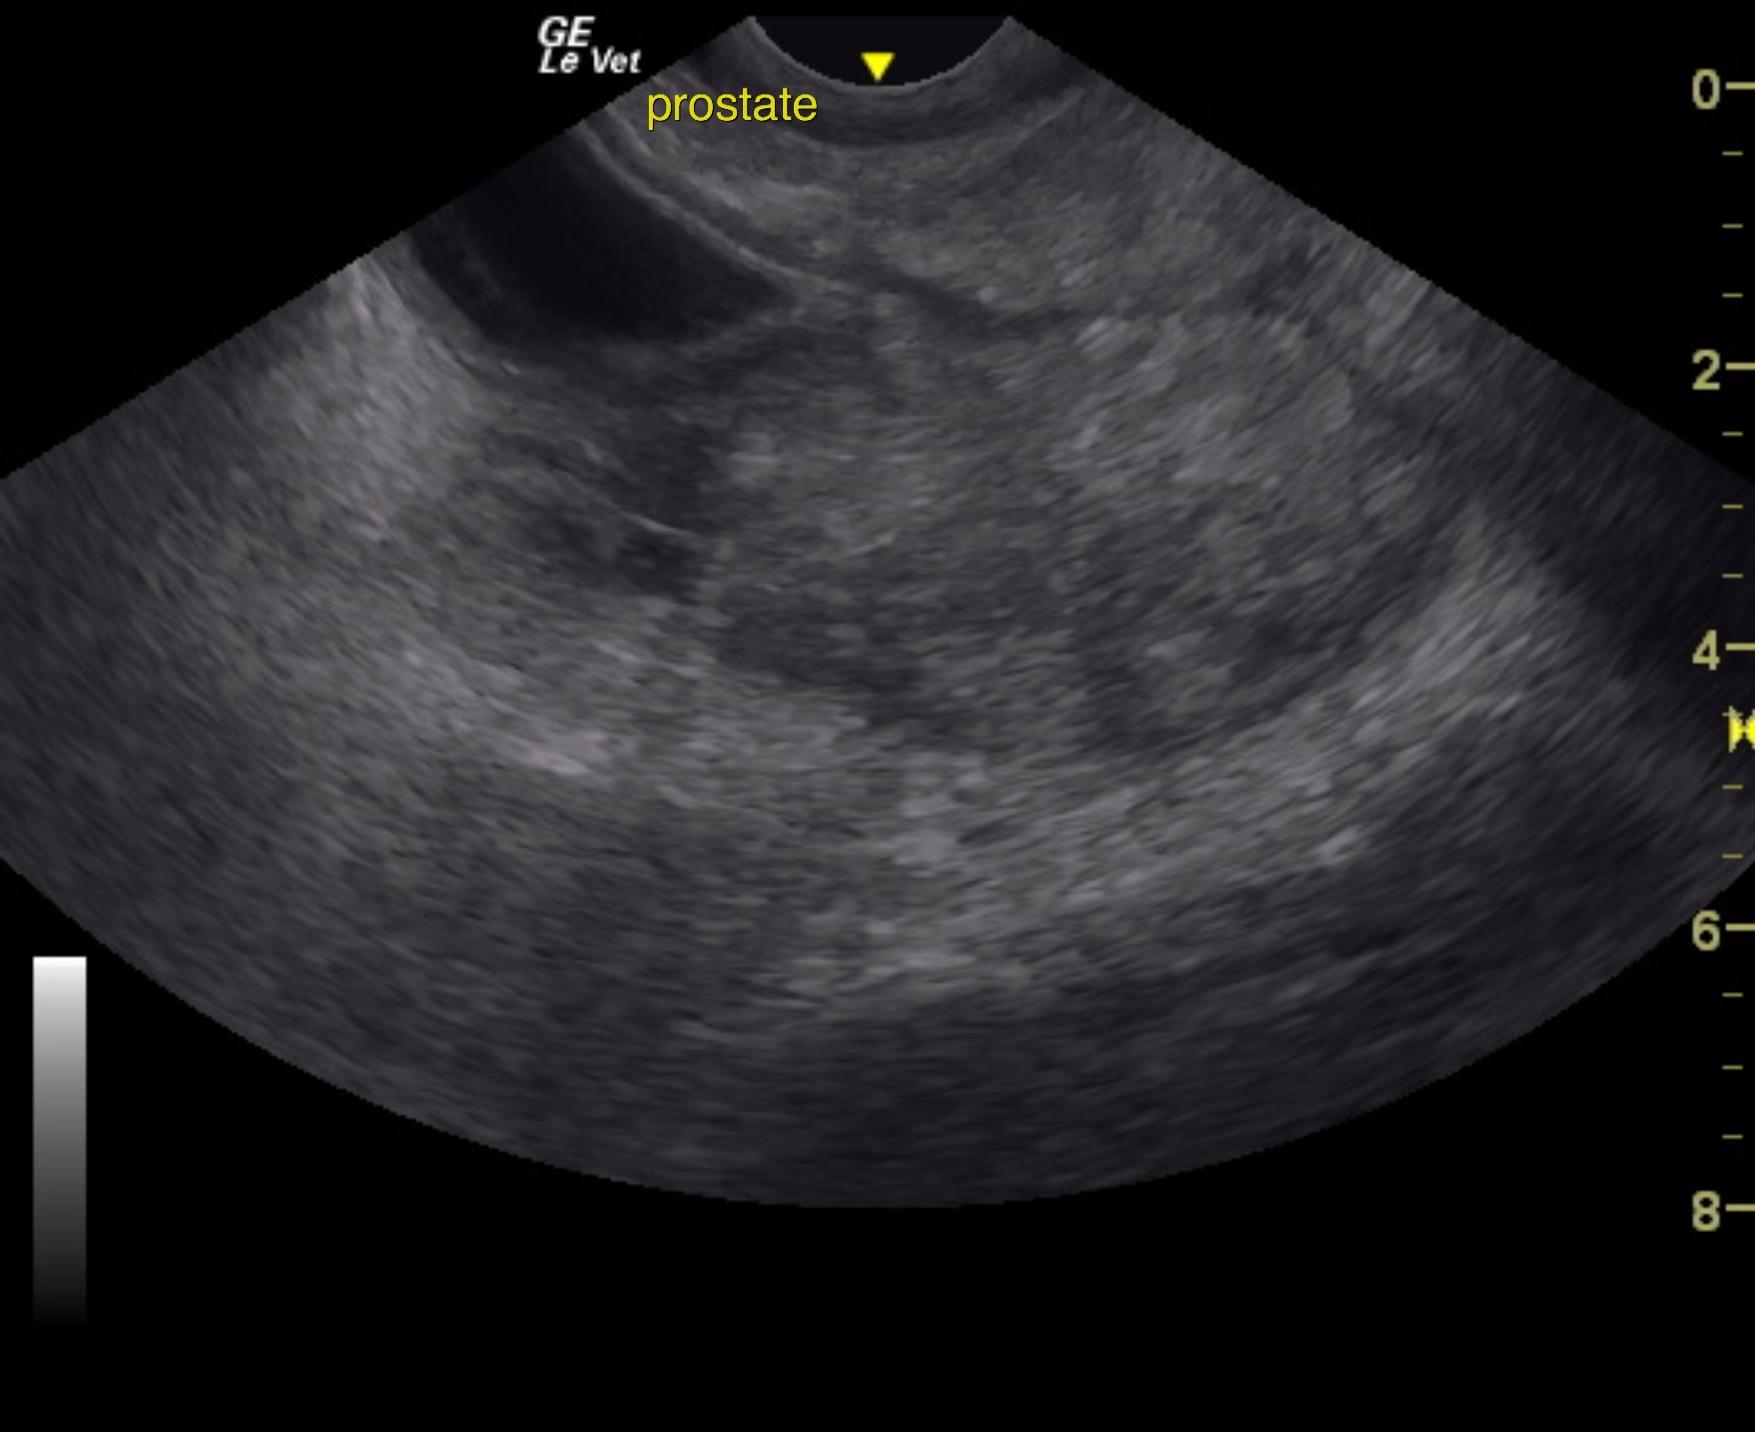

An 11-year-old NM Labrador with a history of gradual weight loss was presented for evaluation of abdominal pain and diarrhea. On abdominal palpation, the intestines were gas-filled, which was confirmed on survey radiographs. Elevated ALT activity, BUN, and glucose were present on serum biochemistry.